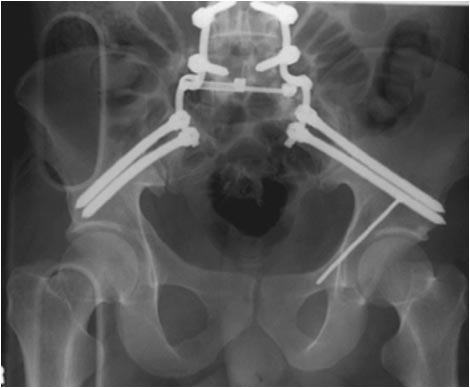

[Ortho] Тяжелое повреждение таза

Вам надо начинать сзади. Пример в файле.